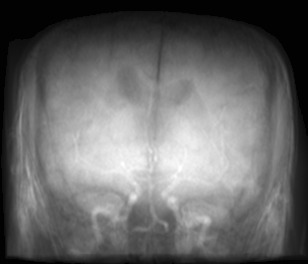

(a) Guide 𝑮𝑮\boldsymbol{G}

(b) Input 𝑰𝑰\boldsymbol{I}

(c) Guidance map 𝑴𝑴\boldsymbol{M}

(d) Prediction 𝑷𝑷\boldsymbol{P}

(e) Ground truth

(f) Guide 𝑮𝑮\boldsymbol{G}

(g) Input 𝑰𝑰\boldsymbol{I}

(h) Guidance map 𝑴𝑴\boldsymbol{M}

(i) Prediction 𝑷𝑷\boldsymbol{P}

(j) Ground truth

Figure 2: Inputs and outputs of the guided filtering pipeline based on the WDSR network. T1 & T2 MRI pairs (a)-(e) and CT & MRI projection images (f)-(j).